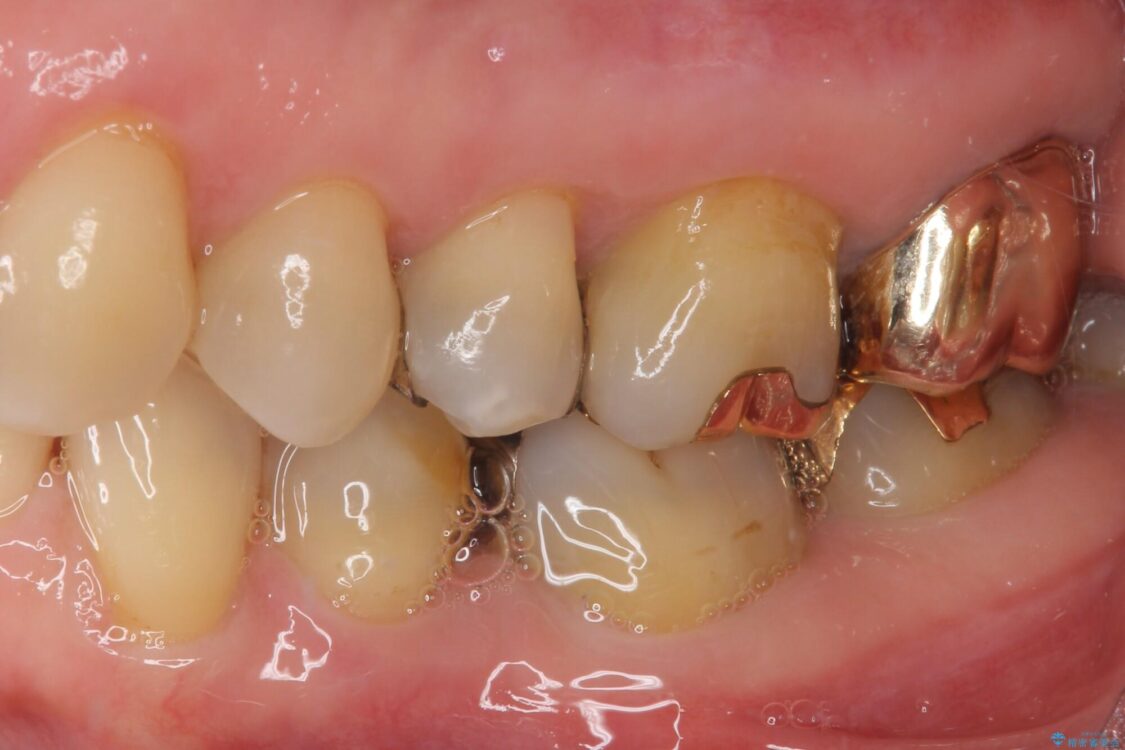

奥歯の銀歯が外れてしまったため、セラミック治療を希望された患者様です。

セラミックインレーによる修復治療を実施しました。

正面から見える場所であったため、セラミックインレーで自然な口元にすることができました。

治療前

• 外れてしまった銀歯 セラミックインレーで自然な仕上がりに 治療前画像